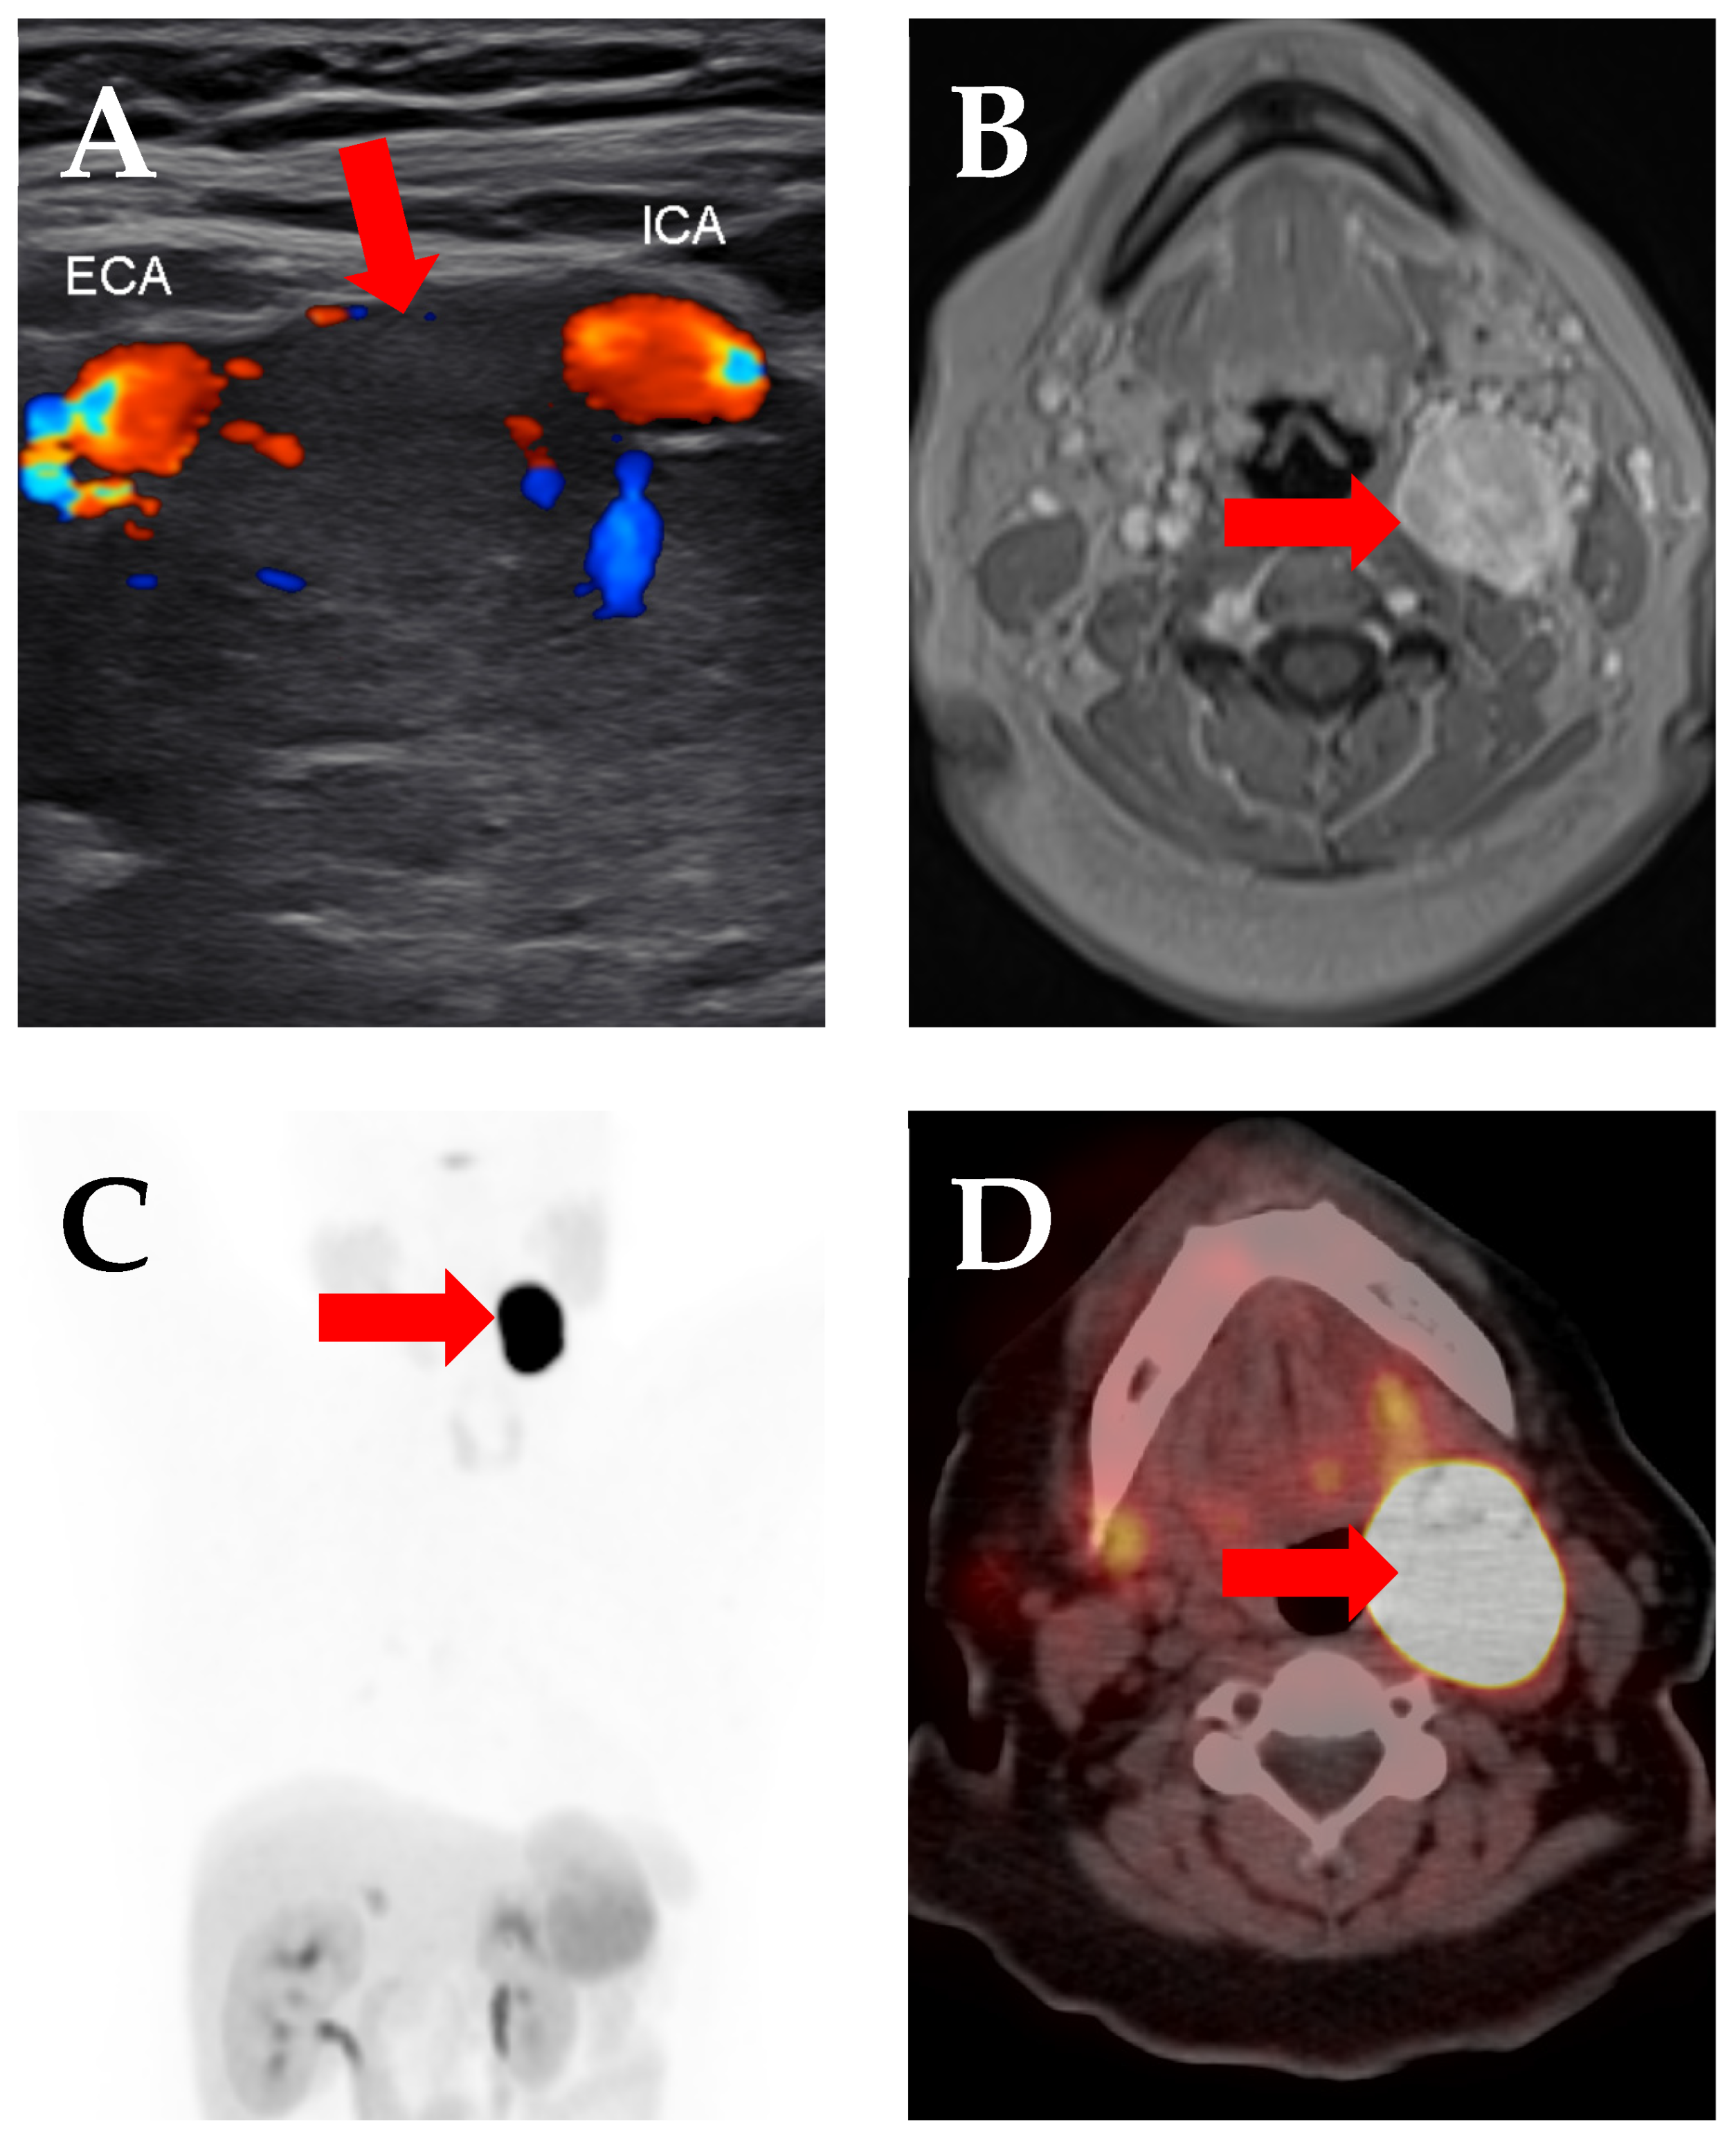

3. Prostate-Specific Membrane Antigen (PSMA)